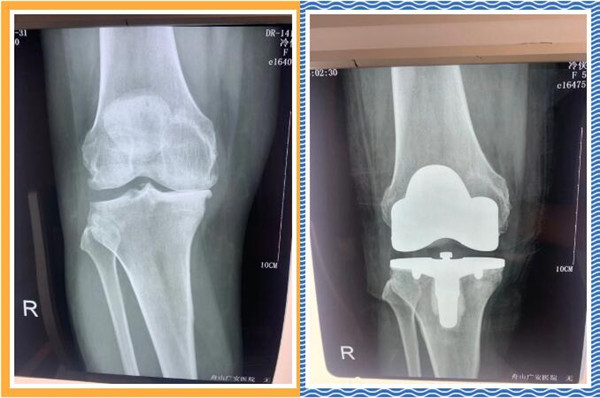

經(jīng)查體及拍片檢查后,危立軍副院長(zhǎng)認(rèn)為冷大姐是右膝關(guān)節(jié)嚴(yán)重磨損,是年輕時(shí)干重體力工作導(dǎo)致關(guān)節(jié)提前磨損,年紀(jì)是輕了一點(diǎn),但關(guān)節(jié)置換是一種相對(duì)較好的辦法,可早期恢復(fù)關(guān)節(jié)正常,改善生活質(zhì)量,建議其入院并接受人工膝關(guān)節(jié)表面置換手術(shù)。。

三天后,冷大姐接受了右膝關(guān)節(jié)置換手術(shù)。手術(shù)由危立軍副院長(zhǎng)主刀,在關(guān)節(jié)鏡下順利完成。術(shù)后,冷大姐恢復(fù)良好。同時(shí),在經(jīng)過院部協(xié)商后,減免了冷大姐的部分手術(shù)費(fèi)用和住院治療費(fèi)用。出院那天,冷大姐熱淚盈眶,感謝的話說了又說。